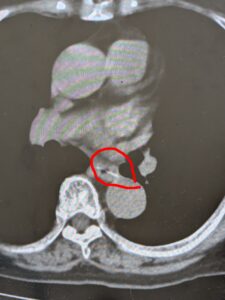

CTで白く見えているものがPTPです。